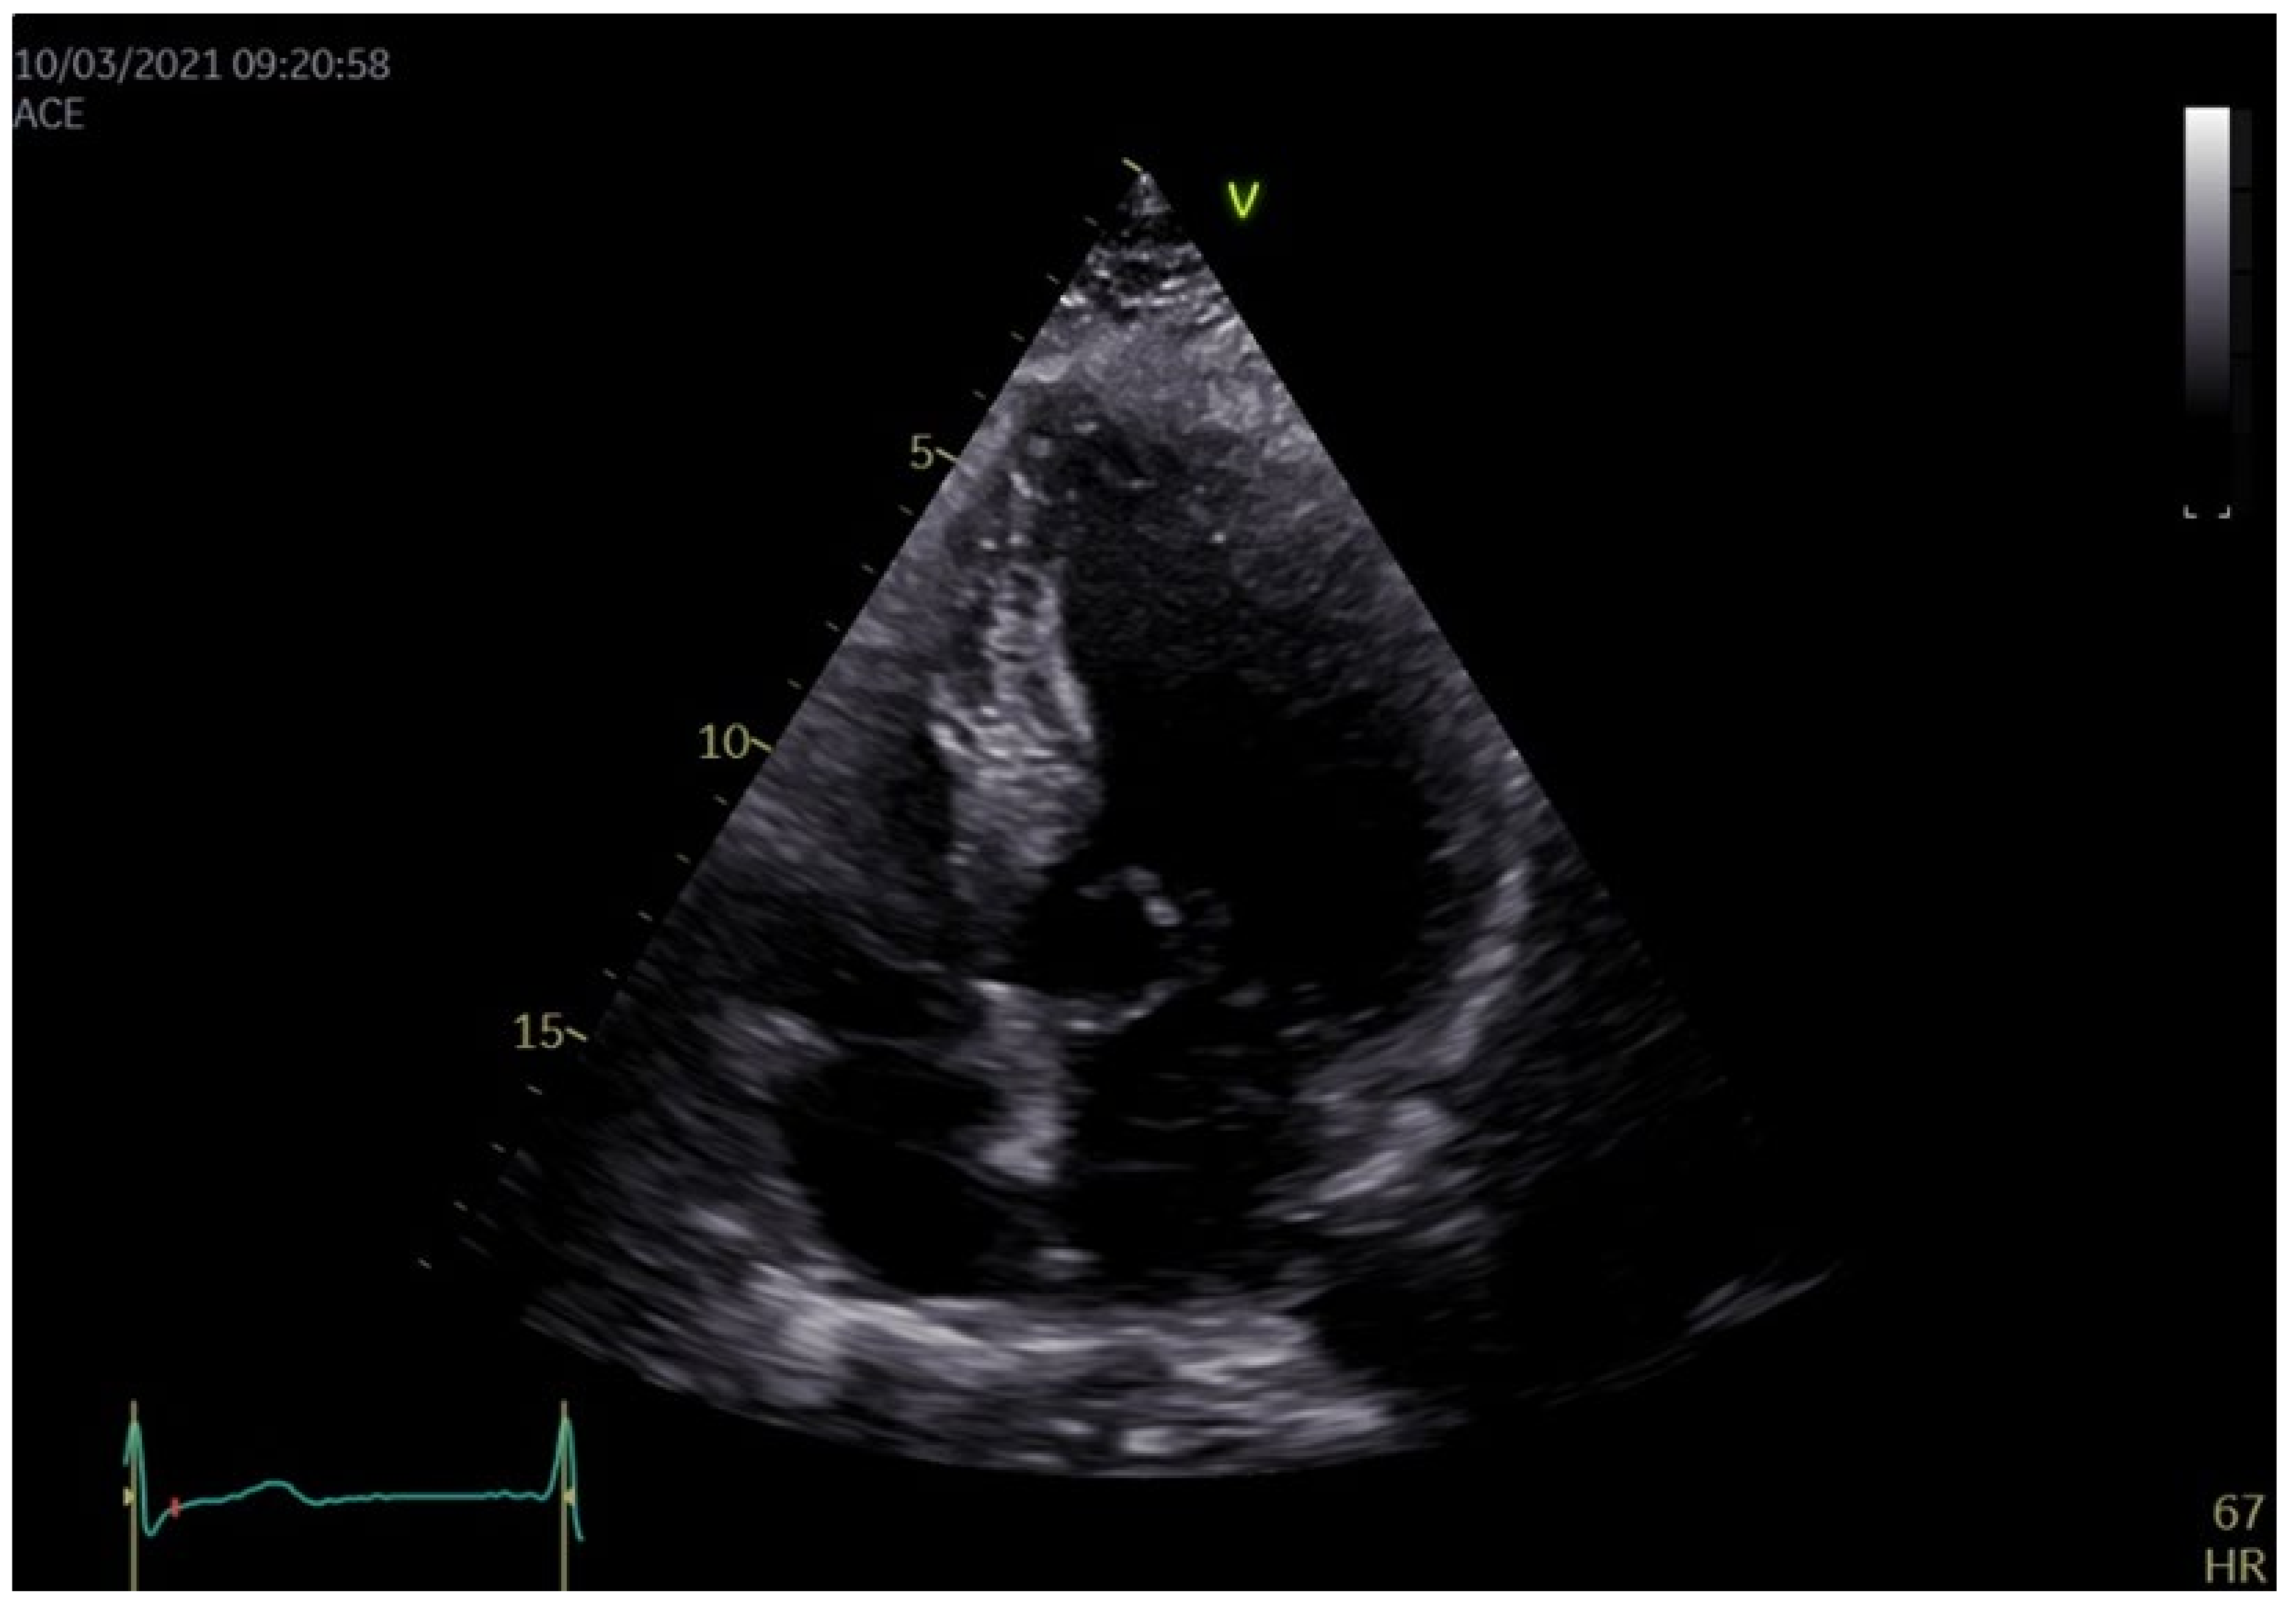

| Parameter | Value/Structure and Function Alteration |

|---|---|

| Chambers quantification | |

| Interventricular septum (IVS), mm | 21 |

| Left ventricular posterior wall (LVPW), mm | 15 |

| Left ventricular end-diastolic diameter, mm | 44 |

| Left ventricular end-diastolic volume, mL | 90 |

| Left ventricular ejection fraction (LVEF), % | 60 |

| S’ mitral annulus IVS/lateral wall, m/s | 0.08/0.10 |

| LV global longitudinal strain, % | −19.3 altered in the basal segments |

| LV twist, degrees | 8 |

| Left ventricular outflow tract maximal pressure gradient, mmHg | 100 |

| Left atrium (LA) diameter, mm | 49 |

| Right ventricular free wall, mm | 7 |

| Right ventricular diameter, mm | 27 |

| Tricuspid annular plane systolic excursion (TAPSE), mm | 25 |

| S’ tricuspid annulus, m/s | 0.16 |

| Right ventricular fractional area change (RV FAC), % | 40 |

| Valves quantification | |

| Mitral valve | Severe regurgitation |

| Aortic valve | Degenerated |

| Tricuspid valve | Moderate regurgitation |

| Pulmonary systolic arterial pressure, mmHg | 40 |

| Pulmonary valve | Minor regurgitation |